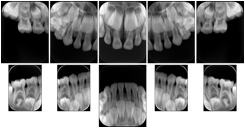

2. A patient requests cosmetic surgery to enhance their facial appearance. The case requires consultation between an orthodontist in New York and an oral surgeon in California. The cephalometric series of 2D projections constructed from the volumetric CT data that is used for the discussion is arranged by a Structured Display for transfer between the two practitioners.

Cephalometric Series Structured Display

Figure OO-2. Cephalometric Series Structured Display